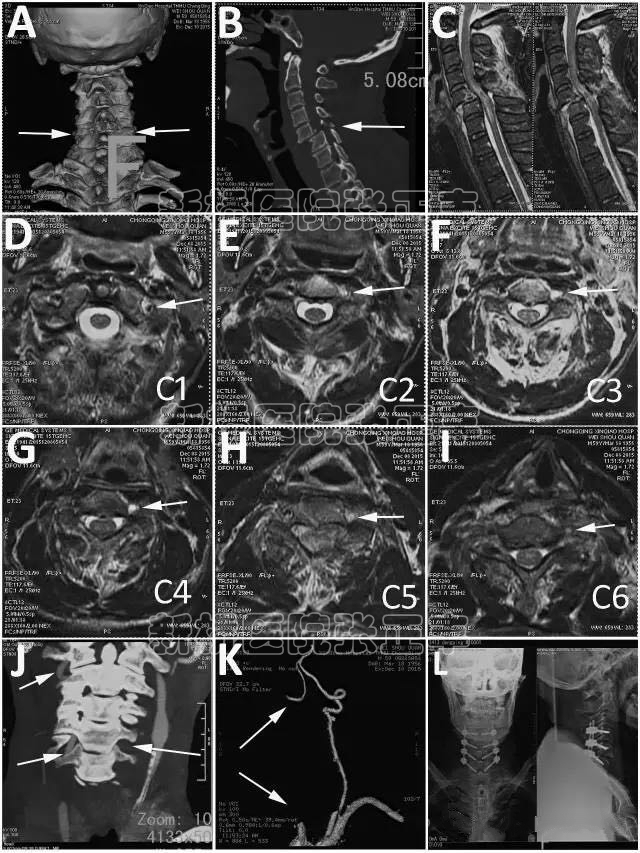

颈椎外伤后椎动脉损伤的发生率报道为19% 到39%,损伤后出现中风、瘫痪或死亡的几率非常小,仅散在个案报道。颈椎退变前路手术中椎动脉损伤的发生率为0.2% 到1.96%。

大多数单侧椎动脉损伤并无症状,即便是优势侧急性损伤,也只有12% 到20%的患者出现椎基底动脉缺血表现,如程度不等的截瘫、 头痛、眩晕、呕吐、构音障碍、吞咽困难、共济失调、视力障碍等。

但是,双侧椎动脉损伤常可能有意识改变、针尖样瞳孔甚至突然呼吸停止、死亡。

颈椎脱位后椎动脉损伤

颈椎脱位伴椎动脉损伤的观察发表过外文,颈椎脱位暴露椎动脉切除钩椎关节和小关节复位方法也发表过外文。由于没有经历过术中椎动脉损伤,没有处理损伤的经验。